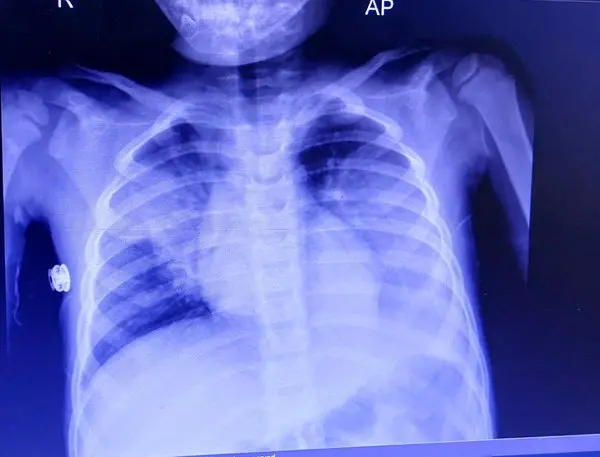

طباطبایی با ابراز نگرانی از شیوع بیماری در تهران و شیراز ادامه داد: ویروس RSV، آدنوویروس و رینوویروسها اکنون شایع شدند که عملا همه این ویروسها را در بیماران تنفسی چک نمیکنیم، اما باید دقت داشته باشیم که کرونا، آنفلوآنزا و RSV امسال شیوع قابل توجهی داشته اند.

طباطبایی دارا بودن نقص ایمنی را در عمده بیماران نقطه مشترک مبتلایان اعلام کردو بیان کرد:امکان تشخیص ویروس به روش پی سی آر وجود دارد؛ ضمن اینکه از لحاظ درمانی نیز برای آنفلوآنزا و ویروس RSV داروی اختصاصی وجود دارد اما به طور معمول استفاده نمیشود؛ مگر در کودکانی که در معرض خطر بیشتری قرار دارند؛ به طوری که اگر شدید باشد بیمار بستری شده و اکسیژن و سرم دریافت میکند.